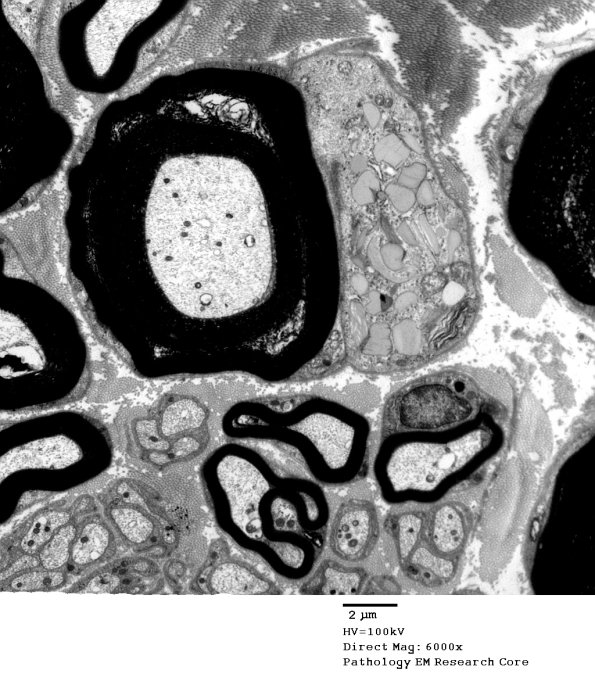

Washington University Experience | PERIPHERAL NEUROPATHY | 3 NORMAL MYELIN & SCHWANN CELLS | 4 Pi Granules (of Reich) | 7A1 Normal Nerve (Case 7) new_042A - Copy

7A1,2 These Pi granules have very little substructure. (Electron micrographs)